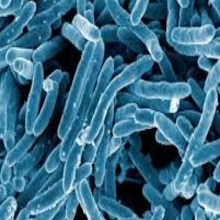

„Mycobacterium tuberculosis" припада роду „Mycobacterium", а фамилији „Mycobacteriае". Немогућност одбојавања алкохолом и киселином (ацидоалкоххолорезистенција) и богатство ћелијског зида липидима су главне карактеристике рода. |